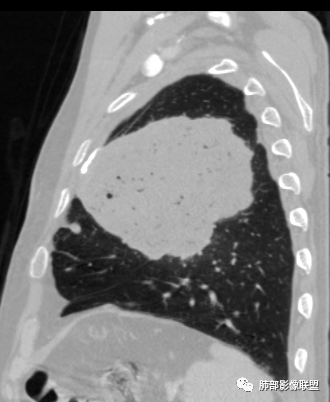

左肺上叶大肿块,膨胀性生长,边界清,密度较低,见部分坏死区,强化弱,肿块见支气管充气V扩张征,分布僵直,枯树枝特点,另一个重要特点血管造影征,淋巴瘤,肿块长轴与胸膜平行,与隐球菌鉴别,隐球荚膜抗原检查,明确诊断经皮肺穿刺。另胸膜钙化(问诊既往有无患胸膜炎病史)。

左肺上叶胸膜下肿块,宽基底与胸膜相连,跨叶裂,边缘清晰膨隆,其内支气管充气,部分扩张、僵直,无明显强化,血管造影征,考虑淋巴瘤,鉴别腺癌

左肺胸膜下巨大占位,跨叶裂,宽基底与胸膜相连,胸膜钙化,平扫密度较低,强化不明显,可见内部血管显影,支气管充气征和扩张,考虑为恶性,倾向于淋巴瘤

大肿块,边缘光滑,深分叶

近端支气管堵塞、推移为主

部分类似于脐凹征

内部支气管扩张

肺动脉推移为主,边缘部分进入

1)部位:周围型或中央型软组织肿块,以周围型为多见,且肿瘤多位于肺上叶。如本例:该肿瘤位于左肺上叶。

2)大小及形态:由于本病恶性程度高,早期症状不明显,发现时肿块均较大。如本例病变巨大。

3)肿块边界和边缘:多较清楚,呈圆形、类圆形,且由于肿块生长速度不均匀,可见分叶,毛刺少见。有报道肿块周围毛玻璃影是多形性癌特征表现。

4)密度:肿块平扫为软组织密度,由于体积较大,内部常见大片状坏死,可出现不规则厚壁空洞或坏死内多发无壁小空洞,坏死多不均匀:坏死灶内可见如柳絮样的斑片样强化灶,坏死边缘与非坏死区分界不清本例坏死较明显,密度不均匀。

5)肿瘤强化方式:肺部恶性肿瘤强化程度与其血供丰富程度相关,血供丰富多强化明显,反之则较差。由于PSC 周边实性部分富血供及内部黏液变性、坏死,增强后肿块多数呈轻-中度边缘环形强化或不均匀小斑片状强化。国外学者对照病理发现肿瘤细胞或胶原组织增强扫描时强化,无强化的低密度区代表了黏液样变性区和出血坏死区。